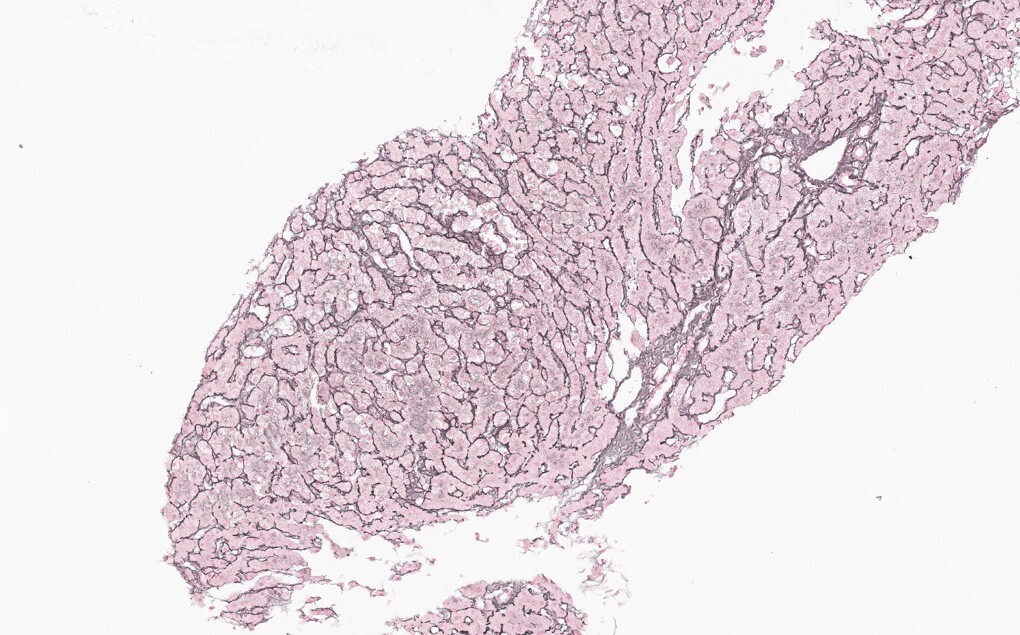

Dans un tiers des cas environ, la MVPS se révèle par une complication de l’hypertension portale (rupture de varices œsophagiennes et ascite, à parts égales).4 Le reste du temps, le diagnostic est posé lors d’explorations d’anomalies du bilan hépatique6 ou à la suite de la découverte fortuite de signes d’hypertension portale (splénomégalie, thrombopénie, varices œsophagiennes ou gastriques, voies de dérivation porto-systémiques en imagerie). Dans tous les cas, le diagnostic nécessite une biopsie hépatique, réalisée préférentiellement par voie transjugulaire (fig. 2 et 3).

La MVPS est en effet définie par l’absence de cirrhose attestée par une biopsie hépatique de bonne qualité, associée à au moins un signe histologique spécifique de MVPS, ou à au moins un signe spécifique d’hypertension portale, ou à au moins un signe histologique non spécifique de MVPS et à un signe non spécifique d’hypertension portale (tableau 2).7 Les signes d’hypertension portale ne sont donc pas systématiquement présents dans la MVPS.8